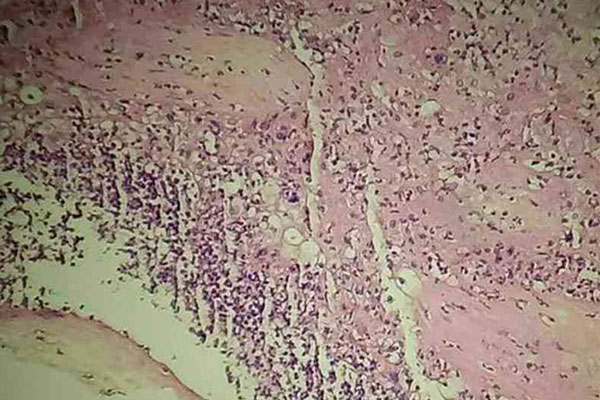

绒毛活检

绒毛活检的话需要在怀孕10到12周的时候,但是通常是在胎儿可能出现与性别相关的严重问题的时候,才会用绒毛活检来辨别胎儿的性别。